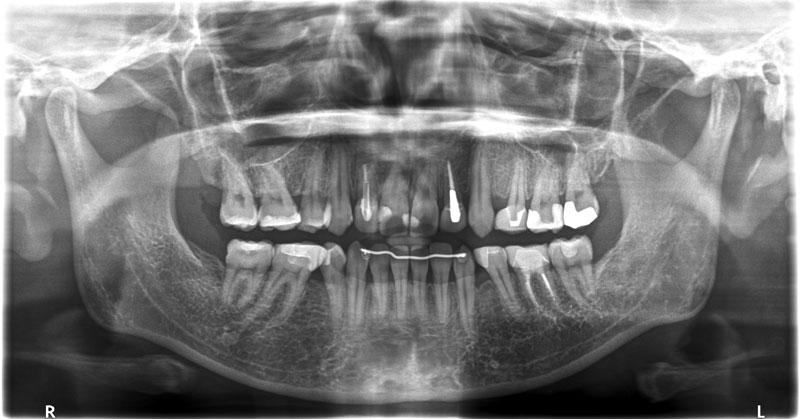

術前

• 初診:2006年、2014年―矯正治療を含めた一口腔単位の治療開始、治療当時、30代女性、非喫煙者

• 治療方針:親知らず3本抜歯、上下小臼歯4本抜歯、矯正用インプラント使用のワイヤー矯正、修復処置、保定(上マウスピース、下ワイヤー)、メンテナンス